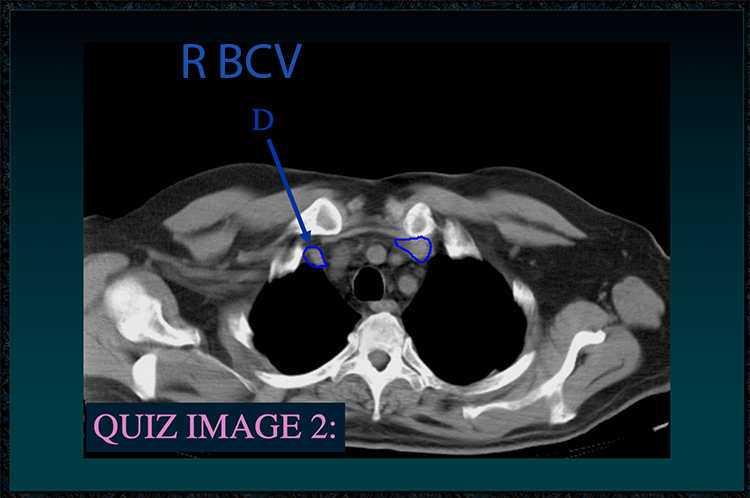

◂Chest Anatomy Review